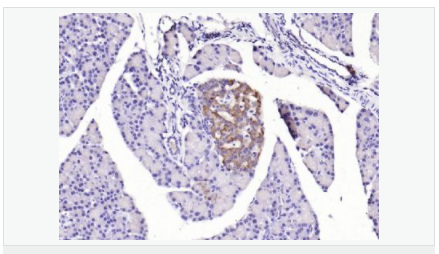

image.png